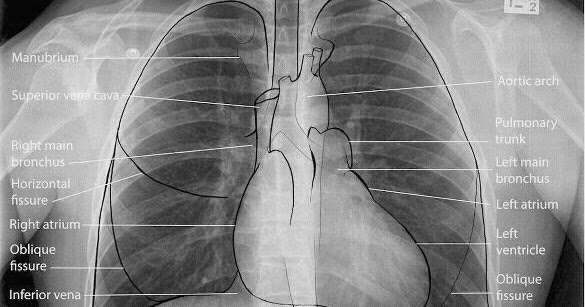

Medical Addicts: Chest X-Ray: Normal PA view